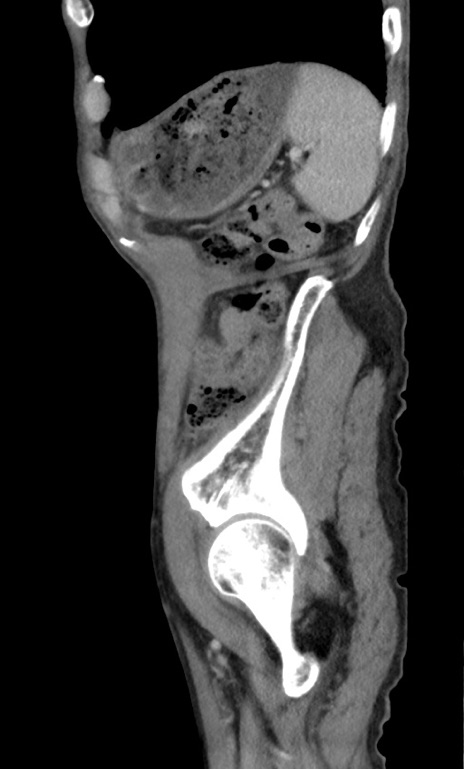

症例3(矢状断像)

【症例】 70歳代男性

【主訴】右鼠径部腫瘤、疼痛

【現病歴】本日朝より上記主訴あり、受診。

【既往歴】膀胱癌にて膀胱全摘、両側尿管皮膚瘻

【データ】WBC 5600、CRP 0.56